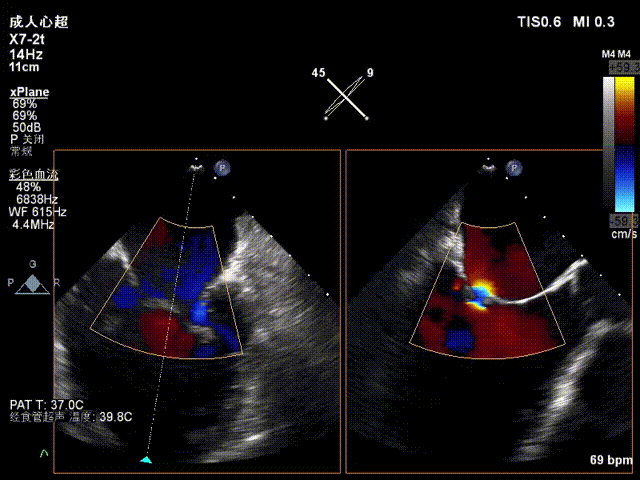

术后超声评估

术后TEE显示二尖瓣双孔化形成,反流明显减少,瓣膜夹位置稳定,二尖瓣跨瓣平均压力阶差为3mmHg,植入后反流显著下降至微量。